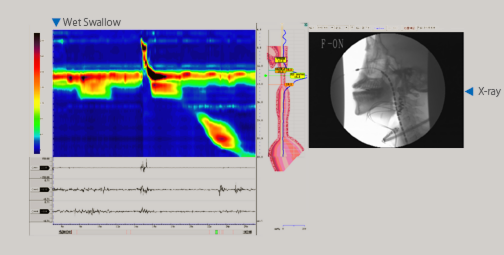

圧力36ch、pH2ch、Z18ch、外部アナログ信号入力16ch、音声1ch、X-ray等のアナログビデオ信号と多種多様な信号をパソコンの1フレームに同時収録します。